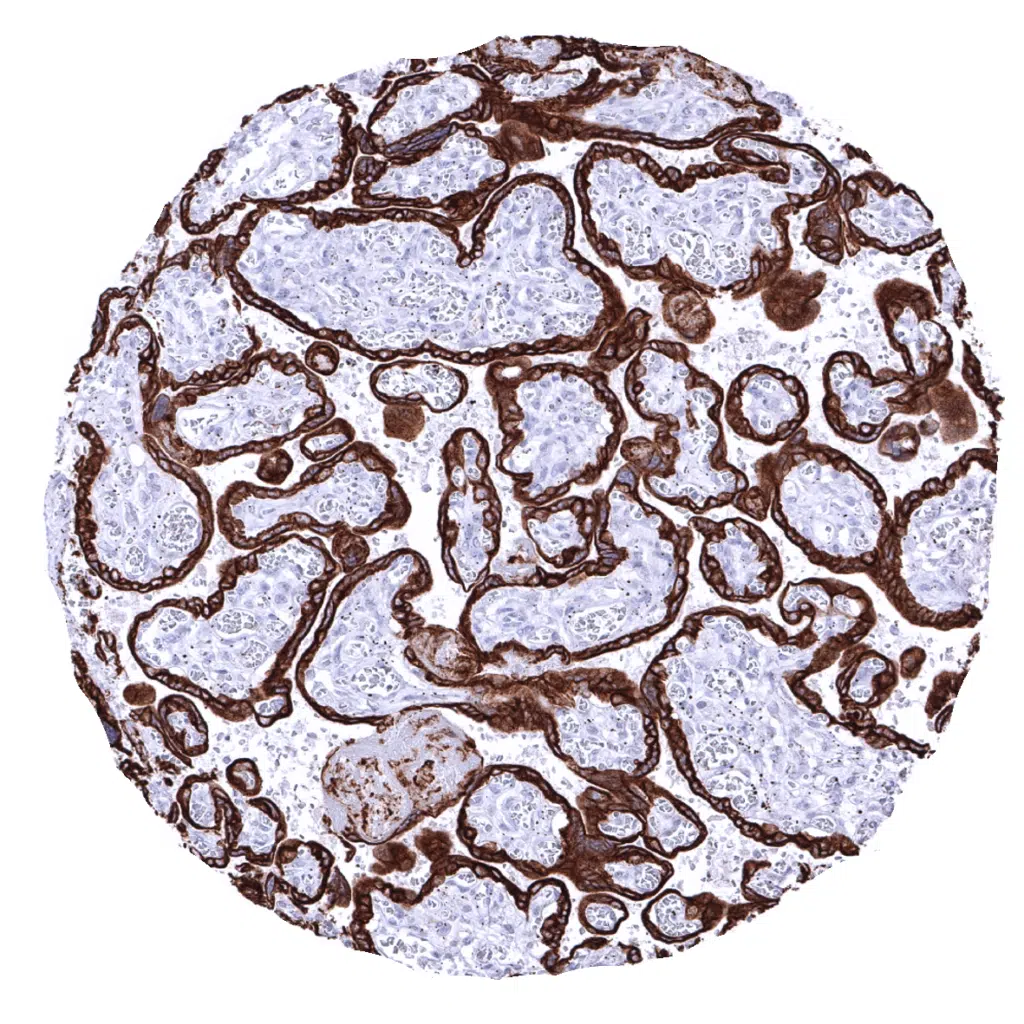

Liver - In the liver, a strong cytoplasmic staining of all bile ductal epithelial cells and an at least moderate, predominantly membranous immunostaining of hepatocytes is seen.

Liver - The pan Cytokeratin immunostaining pattern of hepatocytes can show a zonal variability.